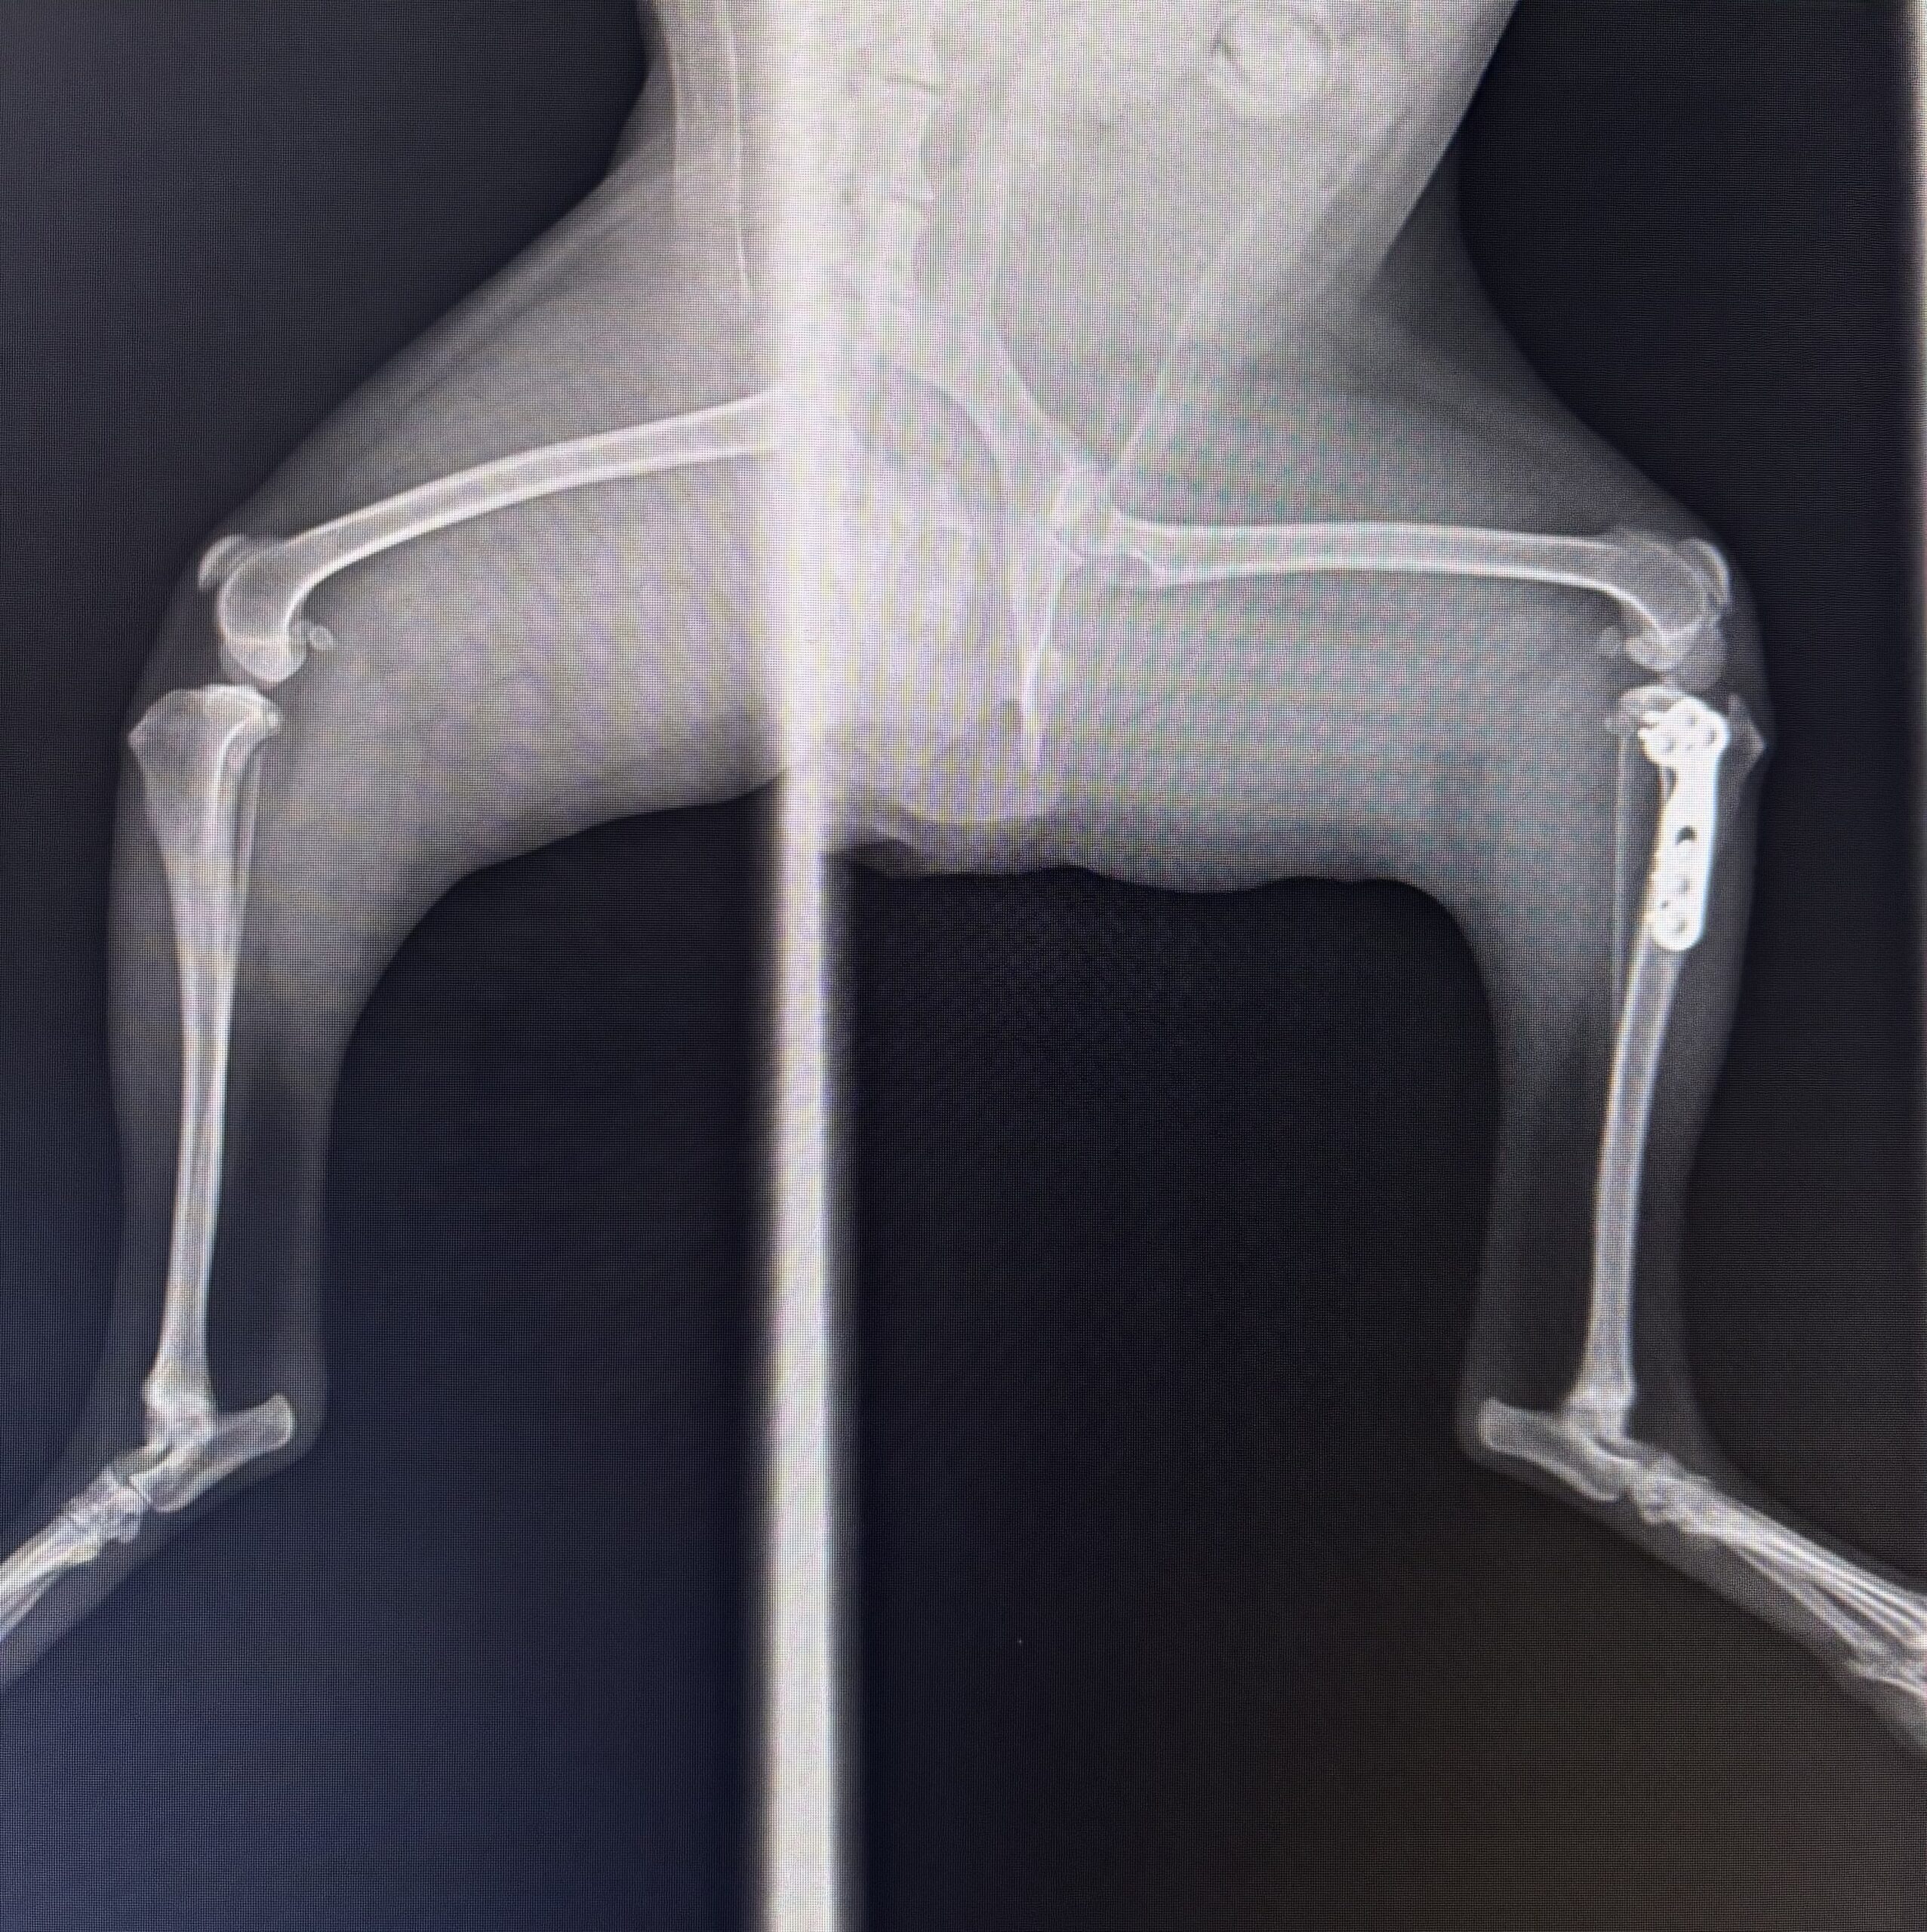

肥満犬における「前十字靭帯断裂」の物理的崩壊

トリミング後の後肢の跛行(足を引きずる状態)は、関節にかかる「力学的な限界」を超えたサインです。

- 解剖学的欠陥:犬の膝の関節面(脛骨高平部)は、人間と違って後ろに向かって大きく傾斜しています。そのため、ただ立っているだけでも大腿骨(太ももの骨)が常に後ろへ滑り落ちようとし、それを前十字靭帯という一本の紐が全力で繋ぎ止めています。

- トリミングによる限界突破:肥満犬の場合、ただでさえ靭帯に過剰な張力がかかり、繊維がほつれて脆くなっています。滑りやすいテーブルの上で数時間踏ん張り続けることで太ももの筋肉が疲労し、体重を支える負荷の全てが靭帯に集中します。その状態で、トリマーが足裏の毛を刈るために片足を持ち上げると、残された軸足の膝関節に「不自然なねじれ(トルク)」と「全体重」が一点集中し、脆くなった靭帯がブチッと断裂します。

- 治療の現実:完全断裂した場合、元の生活に戻すには外科手術が必須となります。大型犬や活動的な犬では、骨を切って関節面の傾斜角度を変える根本治療「TPLO(脛骨高位レベリング骨切り術:数十万円規模)」が推奨されます。小型犬等であれば、人工の太い糸で関節の外側から固定する「関節外制動術(10万〜20万円程度)」という選択肢もありますが、いずれにせよ莫大な身体的・経済的負担を伴います。